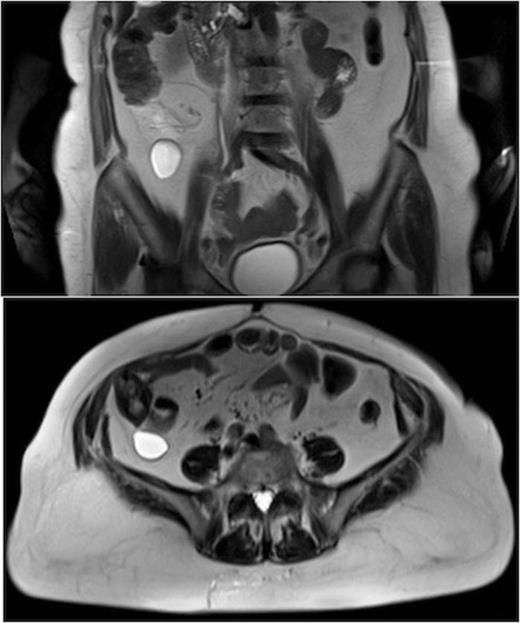

MRI of the abdomen. Axial and coronal T2-weighted TSE images showed the presence of a fluid-filled cystic lesion in the retrocaecl adipose tissue.

During the hospital stay an abdominal MR was performed. The exam revealed in the retrocaecl adipose tissue the presence of a fluid-filled formation with a diameter of 60 mm that appeared indissociable from the caecum for the presence of a tissue connection (Fig 1). Other cystic lesions (communicating with pancreatic duct) were present in the whole pancreas and in the right kidney.